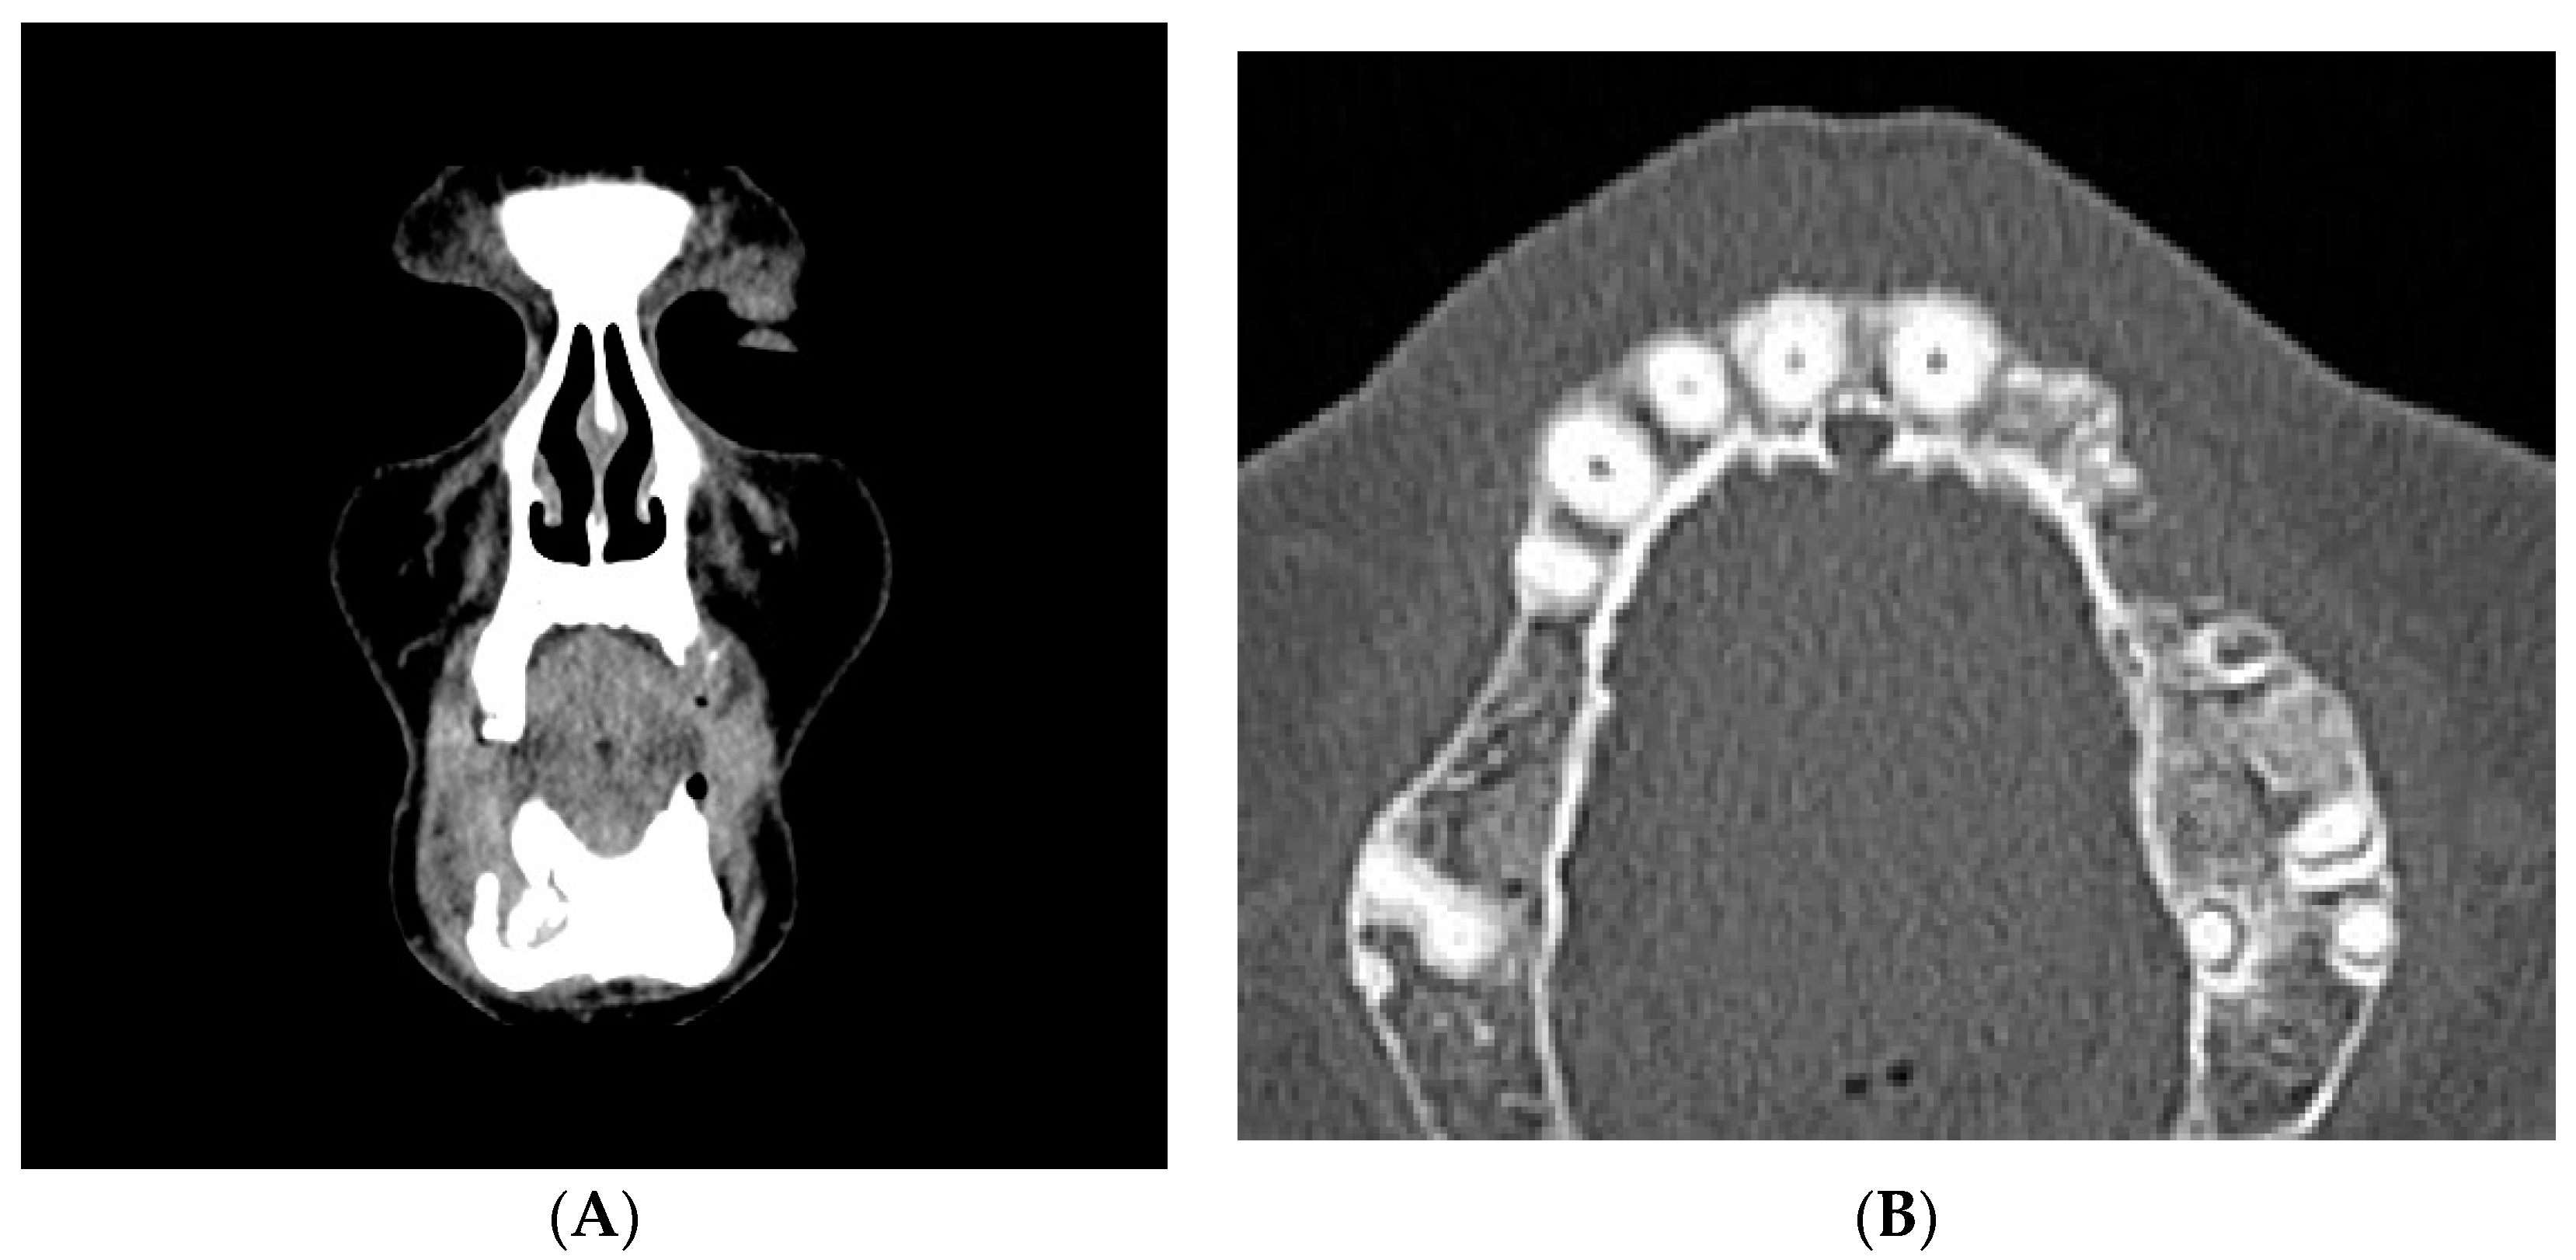

2. Case Report